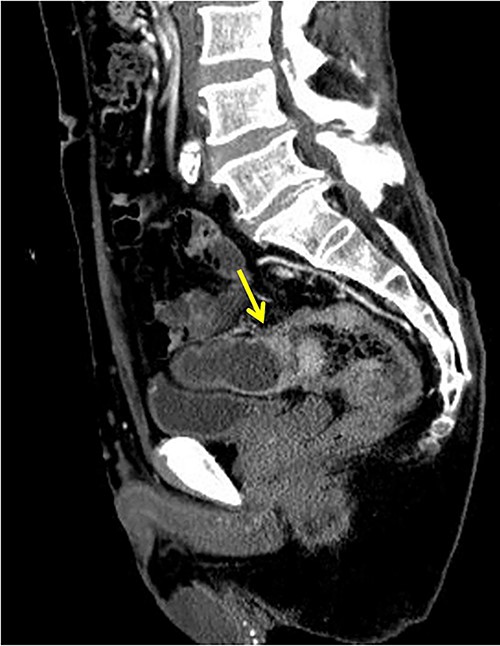

The patient was a 65-year-old man presenting to our hospital with complications of diarrhea for a year and weight loss. Colonoscopy showed rectal cancer on the anal verge (13 cm) with circumferential stenosis. Laboratory findings showed that the serum carcinoembryonic antigen (CEA) level was 4.7 μg/ml and that the serum carbohydrate antigen 19-9 (CA19-9) was 72.2 U/ml. A computed tomography (CT) scan of the abdomen showed thickening of the rectal wall with inflammation. Fistula formation between the ileum and the rectum was observed. Enlarged lymph nodes were also noted around the rectum and no enlarged mesenteric lymph nodes (Fig. 1). The patient was diagnosed with rectal cancer with ileum invasion and then scheduled to undergo surgery. We performed single-incision laparoscopic low anterior resection of the rectum with D3 dissection and partial resection of the ileum. Lymph node dissection, including the area of the inflow vessel, was also performed due to observed lymph node swelling in the mesentery of the ileum around the fistula formation intraoperatively. The operative time was 326 min, and the blood loss volume was 15 ml. Histopathological analysis revealed that the lymph nodes in the small intestine were positive for metastasis, and the diagnosis was pT4b (small intestine) N1 (2/16 (#251, 1/12, #252 1/4, #253 0/0)) M1 (small intestine mesenteric lymph node (1/1)), nonsolid type (por2) adenocarcinoma, ly3, v2 f Stage IV [TNM (tumor, nodes, metastasis) classification] (Fig. 2a and b). After discharge from the hospital, capecitabine plus oxaliplatin was administered for 6 months as adjuvant chemotherapy. The patient has been recurrence-free for 2 years after surgery.

(a, b) Rectal cancer with small intestine invasion and fistula formation.